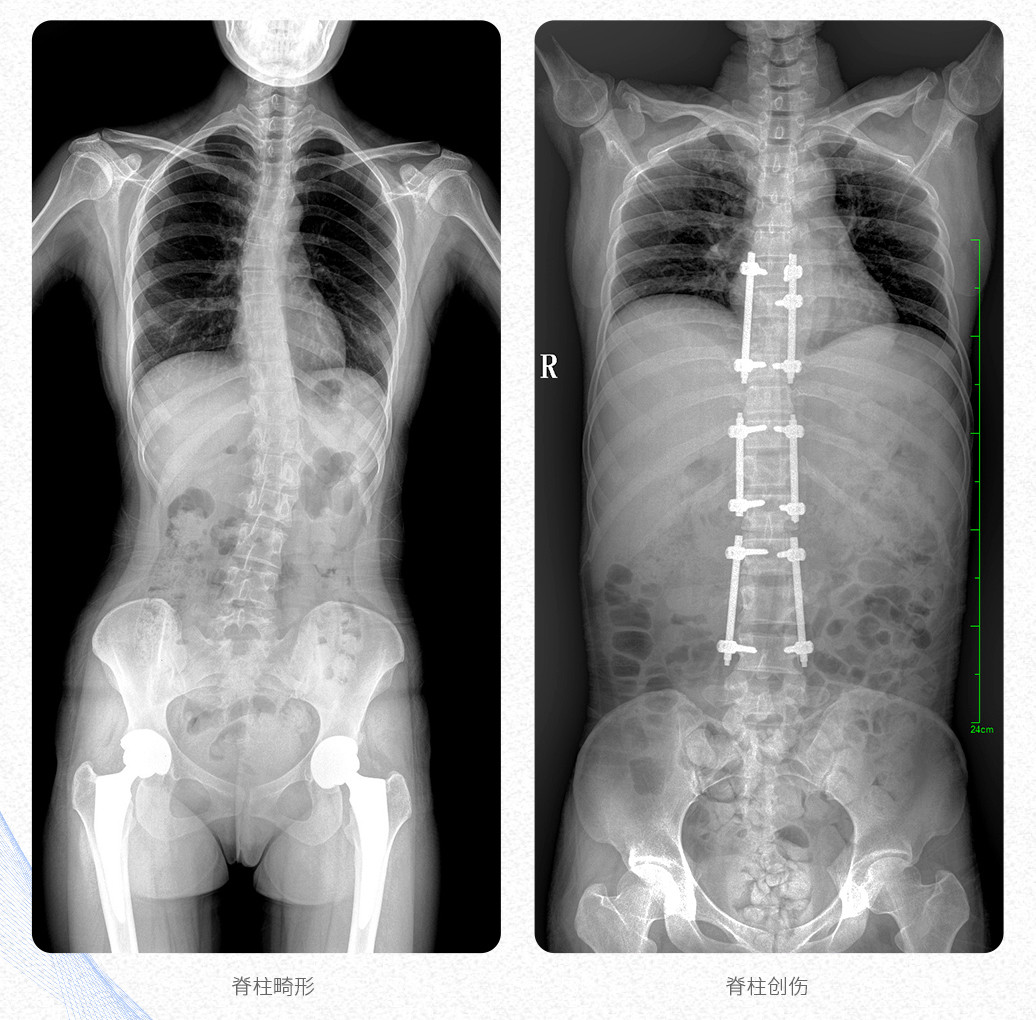

新品PLX8600大視野平板動(dòng)態(tài)DR產(chǎn)品說明:

? ? 普愛醫(yī)療新推出自主研發(fā)的大視野平板動(dòng)態(tài)DR——PLX8600,專為臨床大視野需求打造,圖像不拼接,可有效簡(jiǎn)化影像科室檢查流程,提升工作效率,提高診斷精度,降低臨床拍攝劑量。